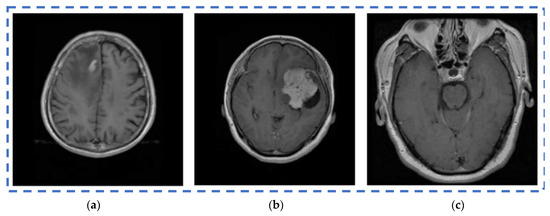

In the proposed segmentation approach, enhanced fuzzy c-means clustering is applied for brain tumor segmentation. In this method, an image’s N pixels are divided into fuzzy c clusters, where c is a positive number and n is a smaller number. Figure 4 and Figure 5 depict various sets of MRI brain images, such as the normal or original image, the binary level image, and the post-morphological operation outcome [37]. The segmentation process is taken as an enhanced version of the fuzzy c-means clustering (EFCMC) algorithm. This includes various stages, as shown in Figure 4 and Figure 5. After performing EFCMC, a final segmented tumor appeared. The proposed segmentation process took less time and was computationally less difficult than other methods.

Figure 4.

Brain MRI images: (a) normal; (b) binary; (c) after a morphological operation.

Figure 5.

Brain images: (a) enhanced; (b) fuzzy c-means 1; (c) fuzzy c-means 2.